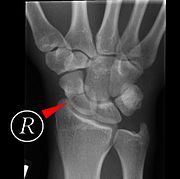

Scaphoid fracture before and after operation

Fractures of the scaphoid are the most common of the carpal bone injuries, because of its connections with the two rows of carpal bones.[1]:177

The scaphoid can be slow to heal because of the limited circulation to the bone. Fractures of the scaphoid must be recognized and treated quickly, as prompt treatment by immobilization or surgical fixation increases the likelihood of the bone healing in anatomic alignment, thus avoiding mal-union or non-union.[5] Delays may compromise healing. Failure of the fracture to heal ("non-union") will lead to post-traumatic osteoarthritis of the carpus.[1]:189 One reason for this is because of the "tenuous" blood supply to the proximal segment.[2] Even rapidly immobilized fractures may require surgical treatment, including use of a headless compression screw such as the Herbert screw to bind the two halves together.

Scaphoid fractures may be difficult to diagnose via plain x-ray, so repeat x-ray may be used at a later date, or cross-sectional imaging via MRI or CT scan.[5]

A condition called scapholunate instability can occur when the scapholunate ligament (connecting the scaphoid to the lunate bone) and other surrounding ligaments are disrupted. In this state, the distance between the scaphoid and lunate bones is increased.[1]:180